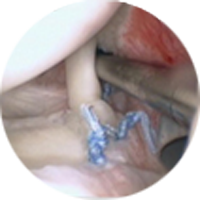

관절와순파열(SLAP)

360도로 돌아가는 어깨관절의 불완전함을 보호하기 위해 관절와순이 관절와를 둘러싸 안정성을 높여주는데 이러한 관절와순이 손상된 질환입니다.

관절내시경 기구를 이용하여 관절와순의 손상된 부분을 절제하여 다듬어 주거나 찢어진 관절와순을 봉합합니다.

관절와순파열

관절와순파열(봉합)